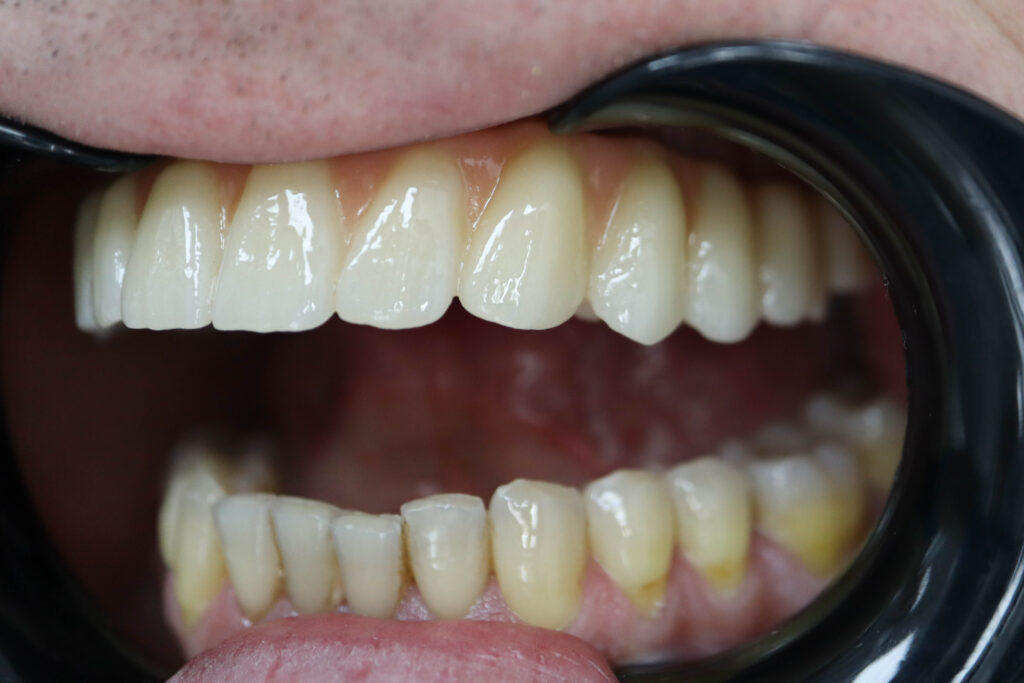

Пациент продолжает лечение спустя 3 месяца после имплантации и установки временного металлоакрилового протеза с опорой на 6-ти дентальных имплантантах Megagen Anyone.

Лечение начато с выбора материала для будущей конструкции (диоксид циркония на титановой балке) и цвета.

Был установлен временный протез из PMMA, максимально воссоздающий форму и цвет (А3) будущей конструкции.

Спустя 25 дней был зафиксирован протез с опопрой на дентальные имплантаты из диоксида циркония с армированием из титана.